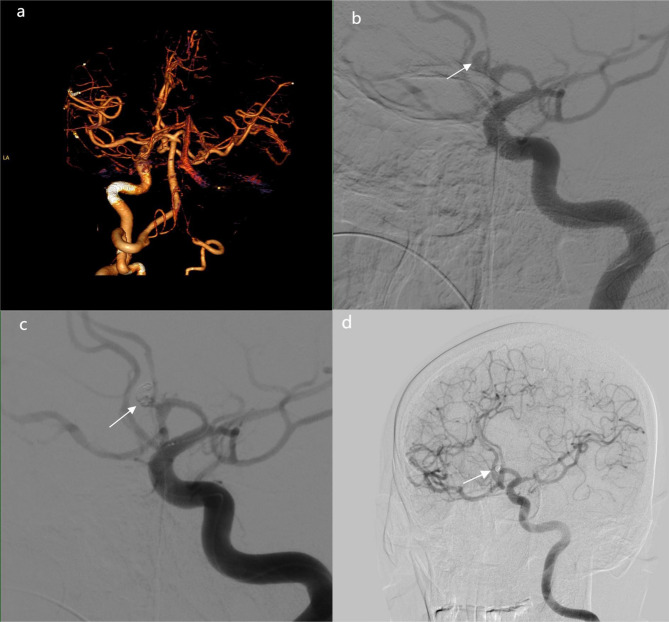

背景:颅内动脉瘤破裂合并颈内动脉闭塞(ICAO)是一种罕见且严重的血管疾病。我们的目的是描述这些患者的临床特征和结果。方法:回顾性分析中国多中心动脉瘤数据库(CMAD)中RIA合并自发性ICAO的病例。采用Logistic回归分析确定与患者预后相关的独立危险因素。采用Cox比例风险模型确定累积死亡率的预测因子。结果:我们分析了52例伴有ICAO的RIA,其中单侧41例,双侧11例。单侧ICAO病例中,同侧8例,对侧16例,中线17例。治疗包括绕线31例,夹持6例,保守处理15例。26例预后良好,17例预后不良,包括12例死亡。Logistic回归发现Hunt-Hess分级IV-V、保守治疗和症状性脑梗死是不良结局的独立危险因素。Cox比例风险模型发现Hunt-Hess分级IV-V是2年随访期间死亡率的预测因子。结论:Hunt-Hess分级、治疗和住院脑梗死独立预测不良结局,IV-V级与早期死亡相关。ICAO可能增加动脉瘤破裂的风险,突出了动脉瘤位置及其相关血流动力学机制在临床管理中的重要性。

Results: We analyzed 52 cases of RIA with ICAO, including 41 unilateral and 11 bilateral cases. Among unilateral ICAO cases, aneurysms were ipsilateral in 8, contralateral in 16, and midline in 17. Treatment included coiling (31 cases), clipping (6 cases), and conservative management (15 cases). Prognosis was favorable in 26 cases and unfavorable in 17, including 12 deaths. Logistic regression identified Hunt-Hess grade IV-V, conservative treatment, and symptomatic cerebral infarction as independent risk factors for unfavorable outcome. Cox proportional hazards model found Hunt-Hess grade IV-V to be a predictor of mortality during the 2-year follow-up.